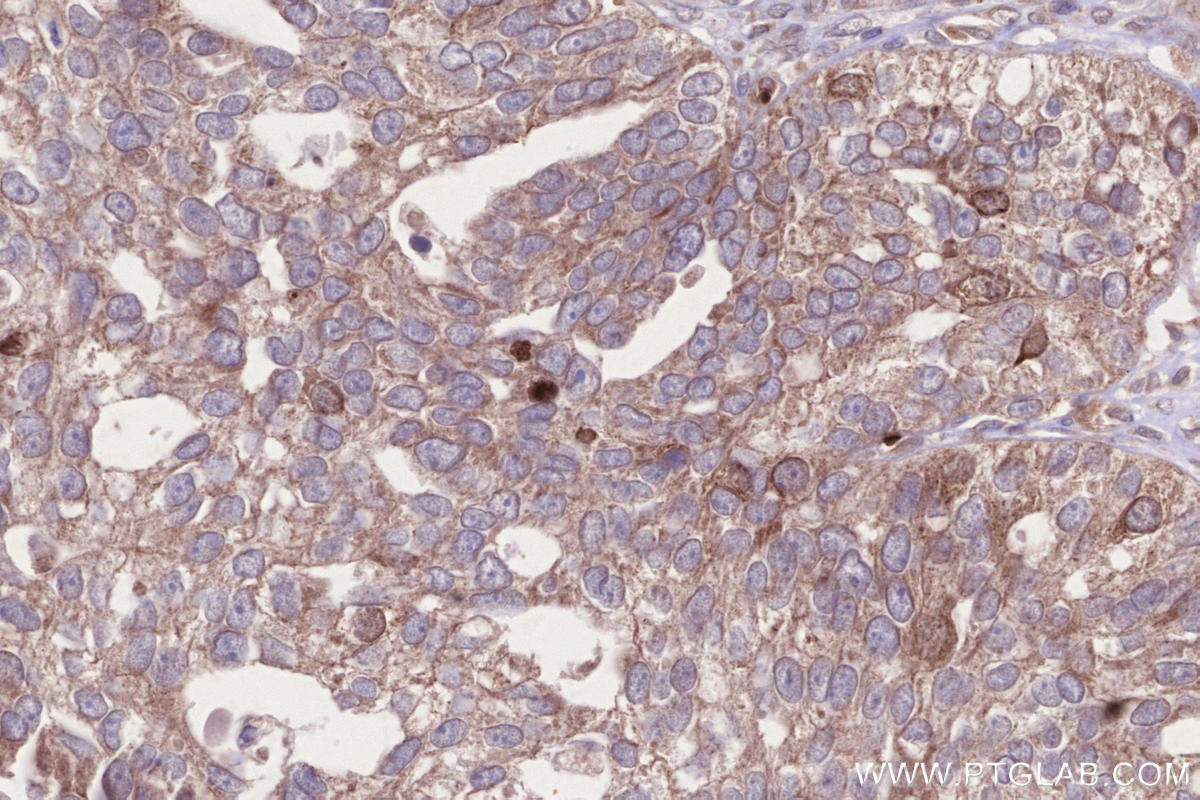

Validation Data Gallery